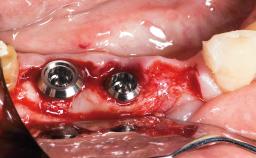

Replacement of Multiple Teeth in a Partially Dentate Posterior Mandible with a Fixed Dental Prosthesis Using an Early Loading Protocol

In 2002, a 27-year-old female patient was referred to our clinic for the treatment of her failing dentition. The patient’s medical history revealed no significant findings that would preclude routine dental procedures. She reported no drug allergies and was currently taking no medications. Her dental history was restricted to operative dentistry that addressed several areas of recurrent decay. The patient was on a periodontal recall and home care program that continually fell short of maintaining a healthy dentition.The patient’s chief complaint was: “My teeth often break, and they are sensitive when I eat and drink.”